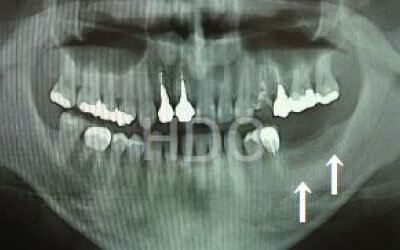

特に、抜けたのが前歯ですとなおさら気になりますよね。 今回のご質問ですが、抜けた部分の骨が薄いなどの理由で「インプラントはできない」と言われた可能性があります。

前歯はもともと骨が薄く、歯が抜けると時間の経過とともにさらに骨が痩せてきてしまうので、インプラント治療の難易度が高い場所です。 ただ結論からお話すると、インプラント治療は可能です。

なぜなら、もし仮に骨が薄くても、骨の治療によって厚みが増せば、安全にインプラント治療が行えるからです。

なお、前歯のインプラント治療をご希望の方には、注意していただきたい点が4つほどあります。 1)インプラント治療を行う前に、骨の治療が必要かもしれません。

2)骨の治療から始めると、その分、治療期間が長くなります。

3)骨の治療は、通常のインプラント治療よりも難易度が高いため、経験の豊富な先生やインプラント認定医のいる歯科医院で治療を受けることをお勧めします。

4)骨の状況をしっかり把握するためにも、CT撮影が必須となります。 また、インプラント治療においては、周囲の歯の状況や咬み合わせの問題などもしっかりと考えて治療するのがとても大切です。